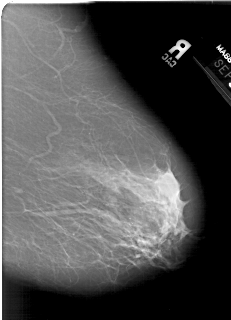

A_1386_1.LEFT_MLO

LEFT_MLO LINES 6421 PIXELS_PER_LINE 4351 BITS_PER_PIXEL 12 RESOLUTION 43.5 OVERLAY